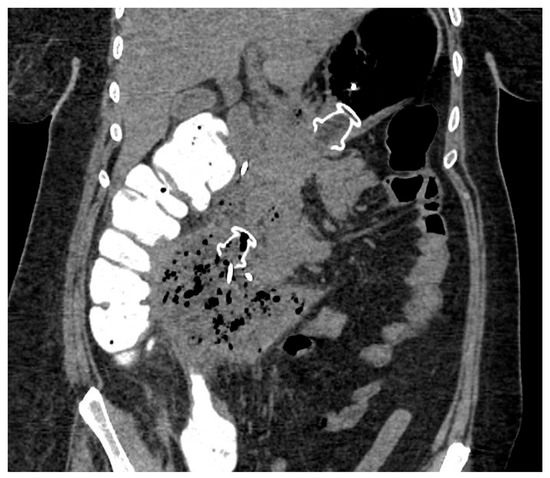

Figure 4.

CT scan image of WON drained endoscopically with multiple transluminal gateway technique, with a transgastric 20 mm and a transduodenal 15 mm LAMS. CT: computed tomography; WON: walled-off necrosis; LAMS: lumen-apposing metal stent.